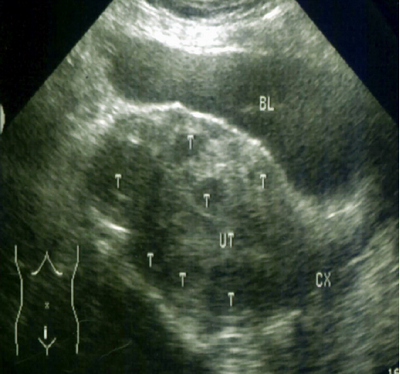

▲ 患者术前彩超图